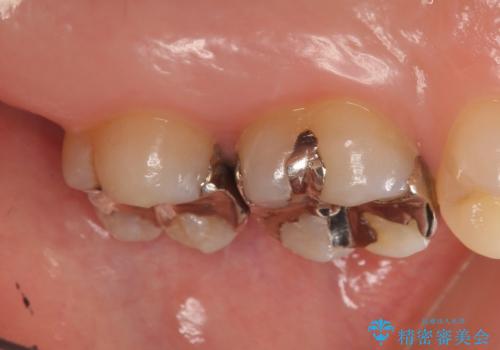

セラミックインレー 銀歯の下の縁下カリエス(歯茎より深い虫歯)の治療

- 左上奥歯がしみるといらっしゃった方の症例です。

左上7近心の虫歯は歯茎より深く、歯茎を下げるため歯周外科を行いました。

術後歯肉の回復を待ち、左下6、7ともにセラミックインレーによる修復を行いました。